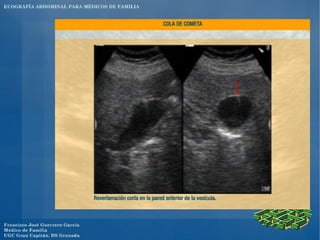

El documento presenta un programa de ecografía abdominal para médicos de familia que incluye presentaciones sobre generalidades de la ecografía y anatomía normal de los órganos abdominales los jueves, y sobre imágenes anormales en ecografía abdominal y ecografía obstétrica los viernes, con un caso clínico el sábado en el centro.